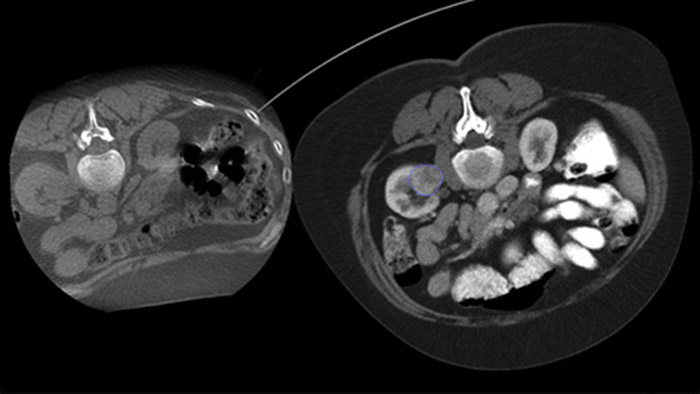

A vista dupla permite a sobreposição de uma imagem 3D pré-procedimento (TC/RM/PET-CT) numa CBCT 3D dual intra-procedimento para melhor visualização das lesões e acesso à entrada crítica para o planeamento da agulha.

Com a CBCT, adquira uma CBCT pós-ablação para demonstrar a extensão da cobertura tumoral e confirmar a integralidade do tratamento.